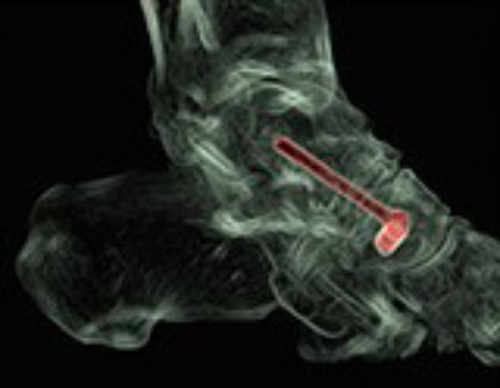

En los casos severos que suelen ser los que acuden a la consulta, si el tratamiento conservador anteriormente descrito no es eficaz en el control del dolor recomendamos la cirugía que consiste en la artrodesis astragaloescafoidea. Es una técnica definitiva que fija la articulación anquilosada ya y dolorosa, mejorando la funcionalidad del pie, aún a pesar de la pérdida de movilidad de inversión y eversión, que puede notarse más al caminar en terrenos irregulares, pero que no es demasiado relevante en la vida urbana.

La artrodesis se realiza con tornillos especiales o sistemas que incluyen dos tornillos cruzados. Habitualmente se inmoviliza con una férula de yeso 2-3 semanas y posteriormente se utiliza una bota de marcha (walker) que se puede quitar para aseo y dormir.

Este periodo de descarga parcial dura unas 6-8 semanas. La carga se hace de forma progresiva y se recupera la vida habitual en torno al tercer mes cuando existe la consolidación de la artrodesis, que en ocasiones se alarga hasta el sexto mes o más.